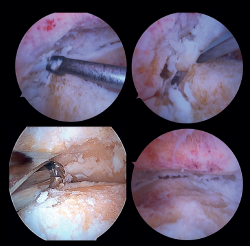

Preparation of the joint surfaces (Figure 4)

- In case of significant synovitis or arthrofibrosis, initial debridement is performed with a synoviotome allowing visualization of the joint.

- Large anterior osteophytes may be present, and their initial resection may require the use of a burr, curette or osteotome, taking care not to damage the anterior neurovascular structures. Resecting them from the start sometimes improves dorsiflexion of the talus and affords a better neutral position in the sagittal plane, as well as better visualization of the operating field.

It is useful to exchange viewing and working portals to access the full extent of the cartilage surfaces and to check complete resection.

The vaporizer is useful in cases of severe fibrotic impingement, which is characteristic of post-traumatic or second surgery scenarios, but again we should work as close to bone or joint space as possible, in order to avoid anterior tissue injury. - It is usually not necessary to use a distraction device to open the joint, since the joint space will progressively grow as the remaining joint cartilage is resected.

- Surgical curettage is performed, with chondral delamination and excision of the cartilage tissue until a viable cancellous bone bed is obtained. This can be done with or without motorized burr support, depending on each case.

- All residues are removed with specific instruments. Perforations can be added to obtain bleeding areas in the subchondral bone.

Figure 4. Preparation of the joint surfaces using different types of instruments: curettes, chisels or motorized drills. Final view after obtaining an optimal subchondral bed of the tibiotalar joint.